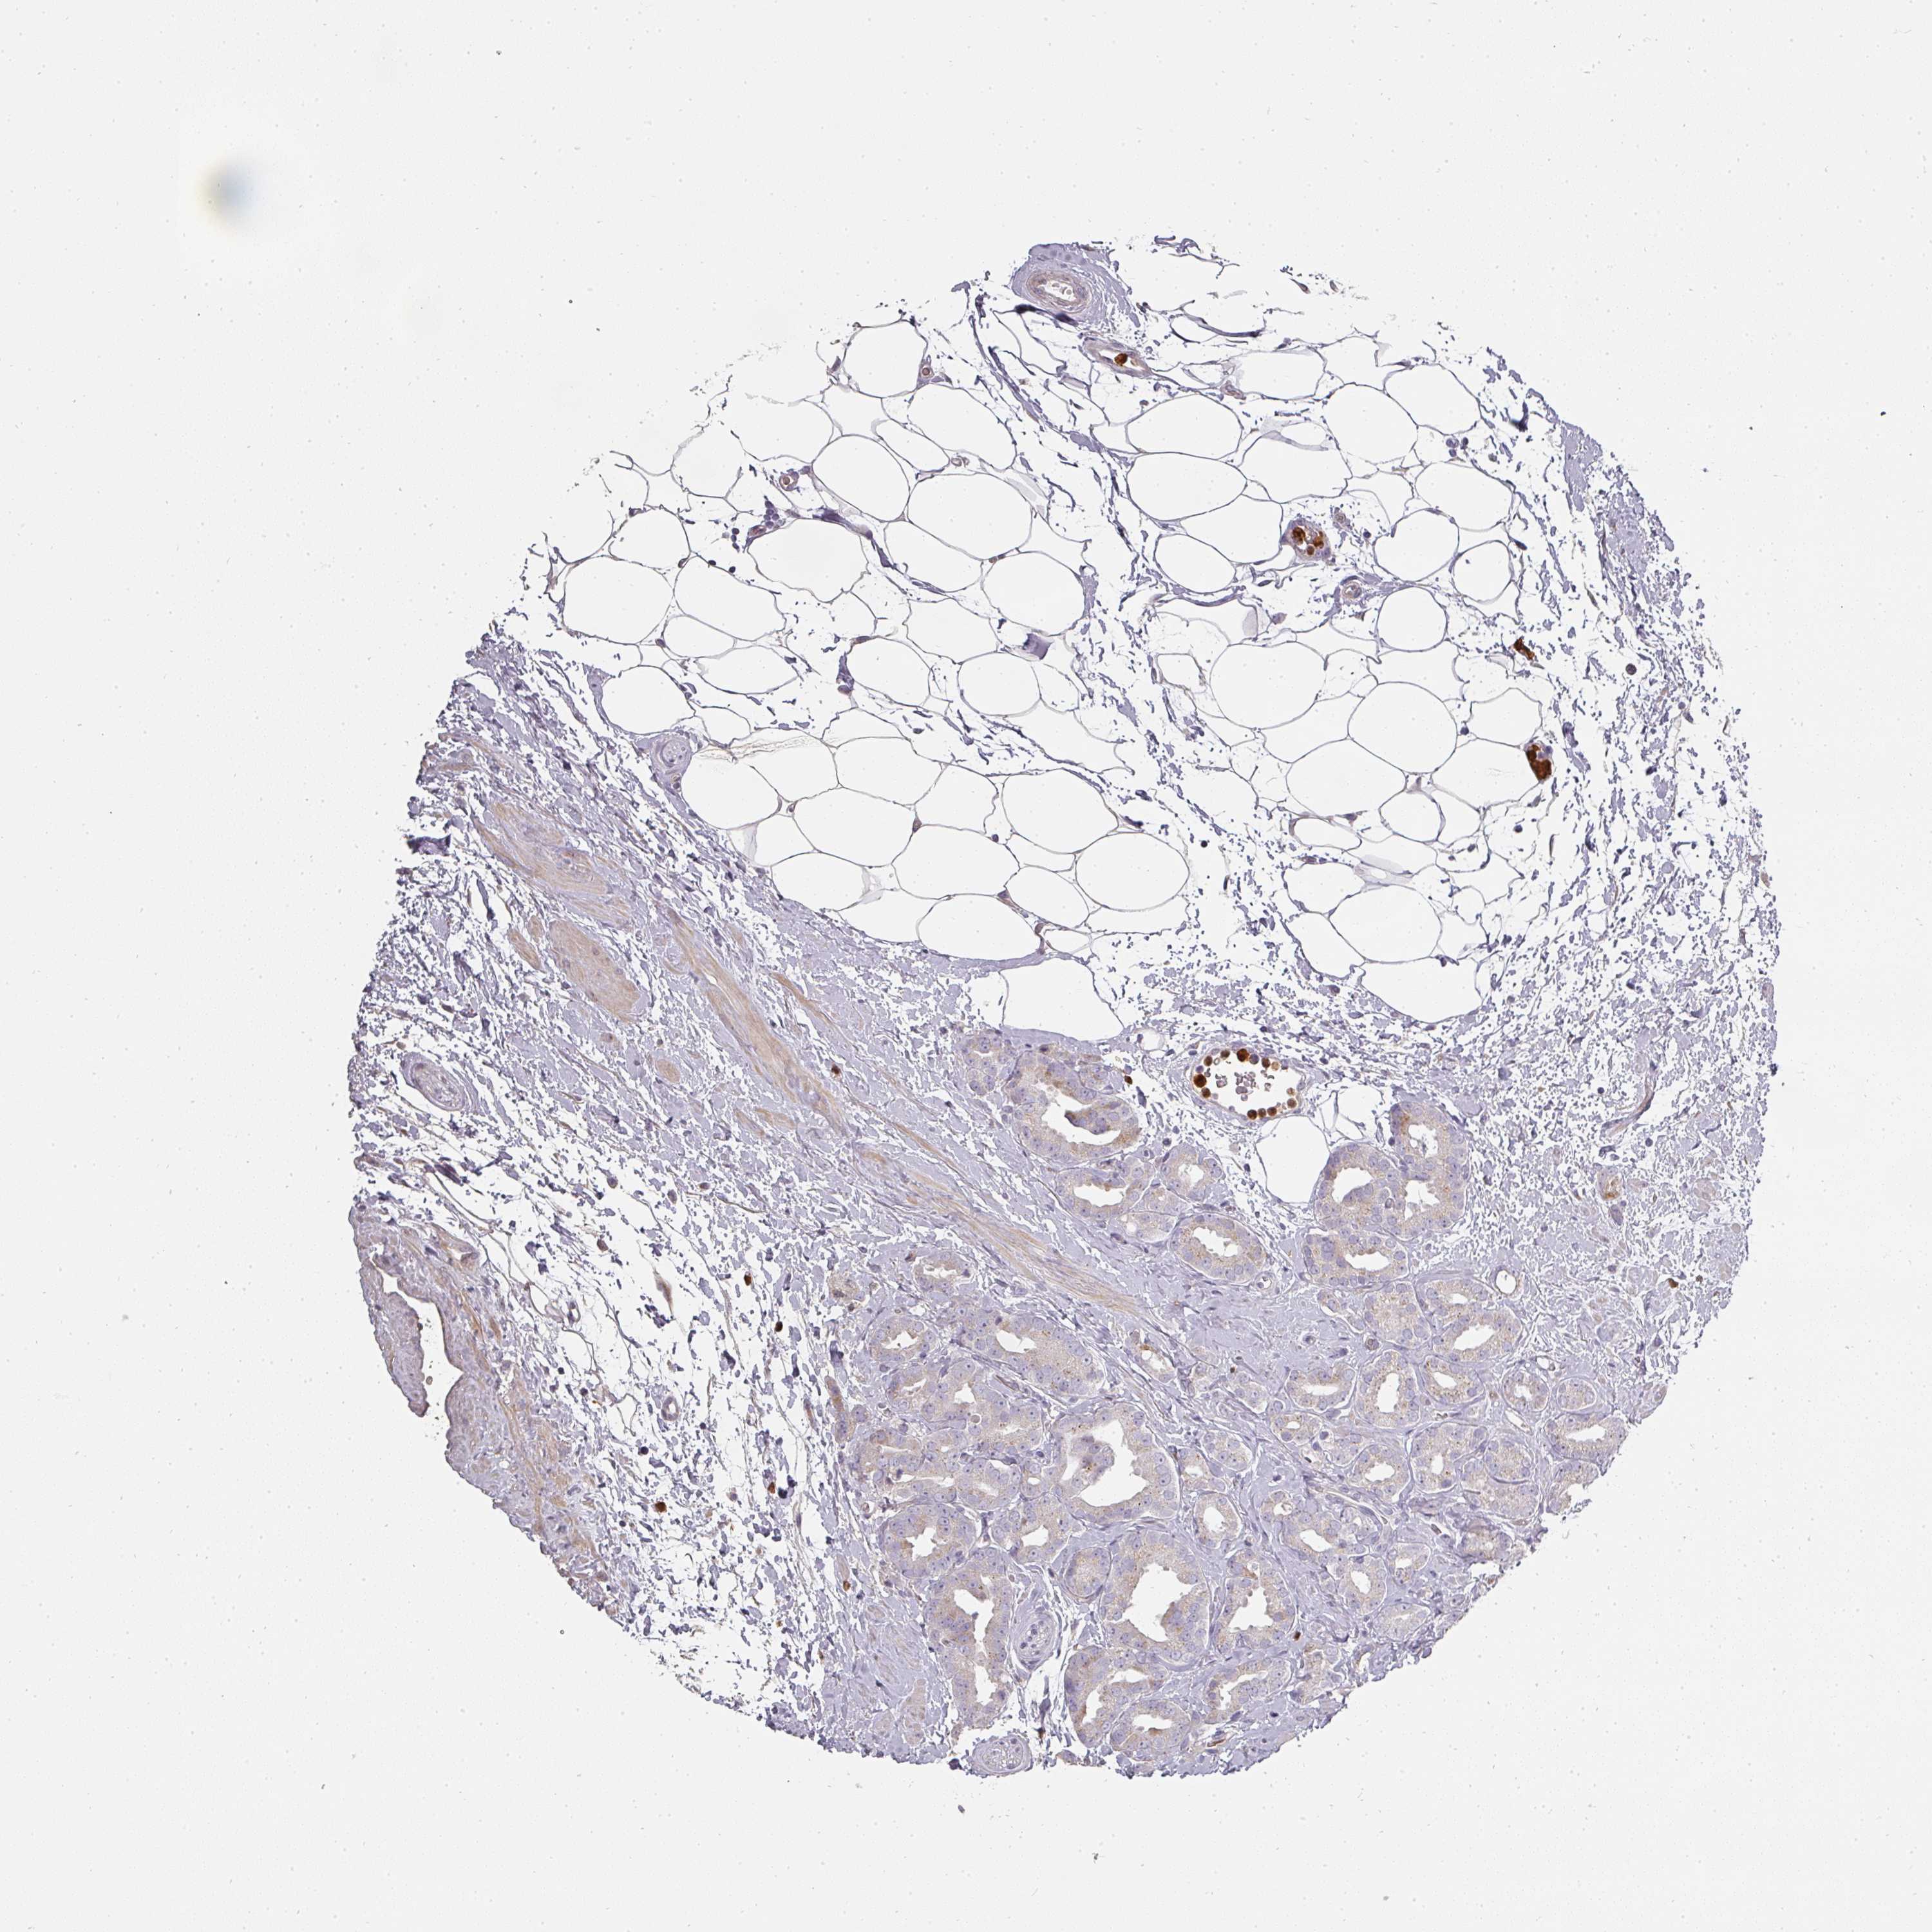

PROSTATE CANCER - Protein expressioni

A mouse-over function shows sample information and annotation data. Click on an image to view it in a full screen mode. Samples can be filtered based on level of antibody staining by selecting one or several of the following categories: high, medium, low and not detected. The assay and annotation is described here.

Antibody stainingi

Antibody staining in the annotated cell types in the current human tissue is reported as not detected, low, medium, or high, based on conventional immunohistochemistry profiling in selected tissues. This score is based on the combination of the staining intensity and fraction of stained cells.

Each image is clickable and will lead to virtual microscopy that enables deeper exploration of all samples and also displays staining intensity scores, fraction scores and subcellular localization as well as patient and tissue information for each sample.

Antibody HPA051360

Staining

High

Medium

Low

Not detected

Intensity

Strong

Moderate

Weak

Negative

Quantity

>75%

75%-25%

<25%

None

Location

Nuclear

Cytoplasmic/membranous

Cytoplasmic/membranous,nuclear

Adenocarcinoma, NOS

Adenocarcinoma, High grade

Adenocarcinoma, Low grade